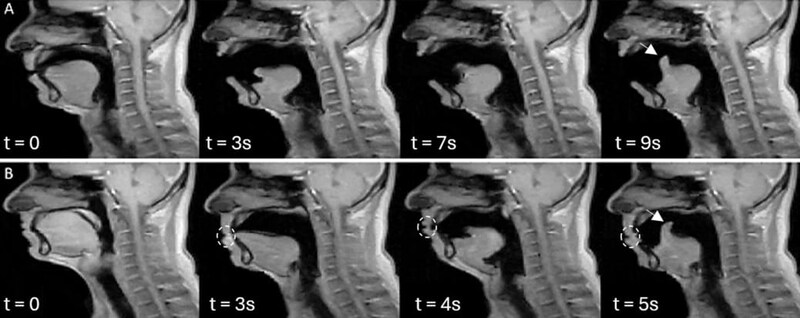

答えを得るため研究チームはまず、健康な大人を磁気共鳴画像装置に入ってもらい、「ふつうの呼吸」「口を大きく開けた深呼吸」「あくび動画を見て自然に出たあくび」「あくびをこらえたとき」の四つの動きをしてもらいました。

もう一つの大きな発見は、「同じ人のあくびの動きが、何度くり返してもほとんど同じだった」という点です。

研究チームは、舌の先の少し後ろの部分を目印にして、その点が時間とともにどんな軌跡を描くかを計算しました。

その結果、一人の参加者の中で、別々のタイミングで出たあくび同士を比べると、その軌跡はとてもよく重なり合い、ほぼ同じ線をなぞっていることが分かりました。

数値としても、動きの似かたを表す指標がほとんどの人で高い値を示しており、なかには「ほぼ完全に一致」と言える人もいました。

さらに興味深いのは、「がまんあくび」の場合です。

参加者が口を閉じてあくびをこらえようとしても、舌の奥のほうの動きのパターンは、口を大きく開けた本物のあくびととてもよく似ていました。

外から見ると控えめなあくびでも、舌やのどの奥では「いつものあくびのプログラム」がちゃんと走っているように見えるのです。